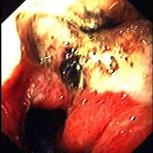

问题 患者,男,50岁,反复上腹痛1年入院。查体:心肺腹未见异常。电子胃镜结果如图,诊断为 ( )

选项 A、胃溃疡并真菌感染 B、胃憩室 C、胃淋巴瘤 D、胃溃疡 E、胃癌

答案 E